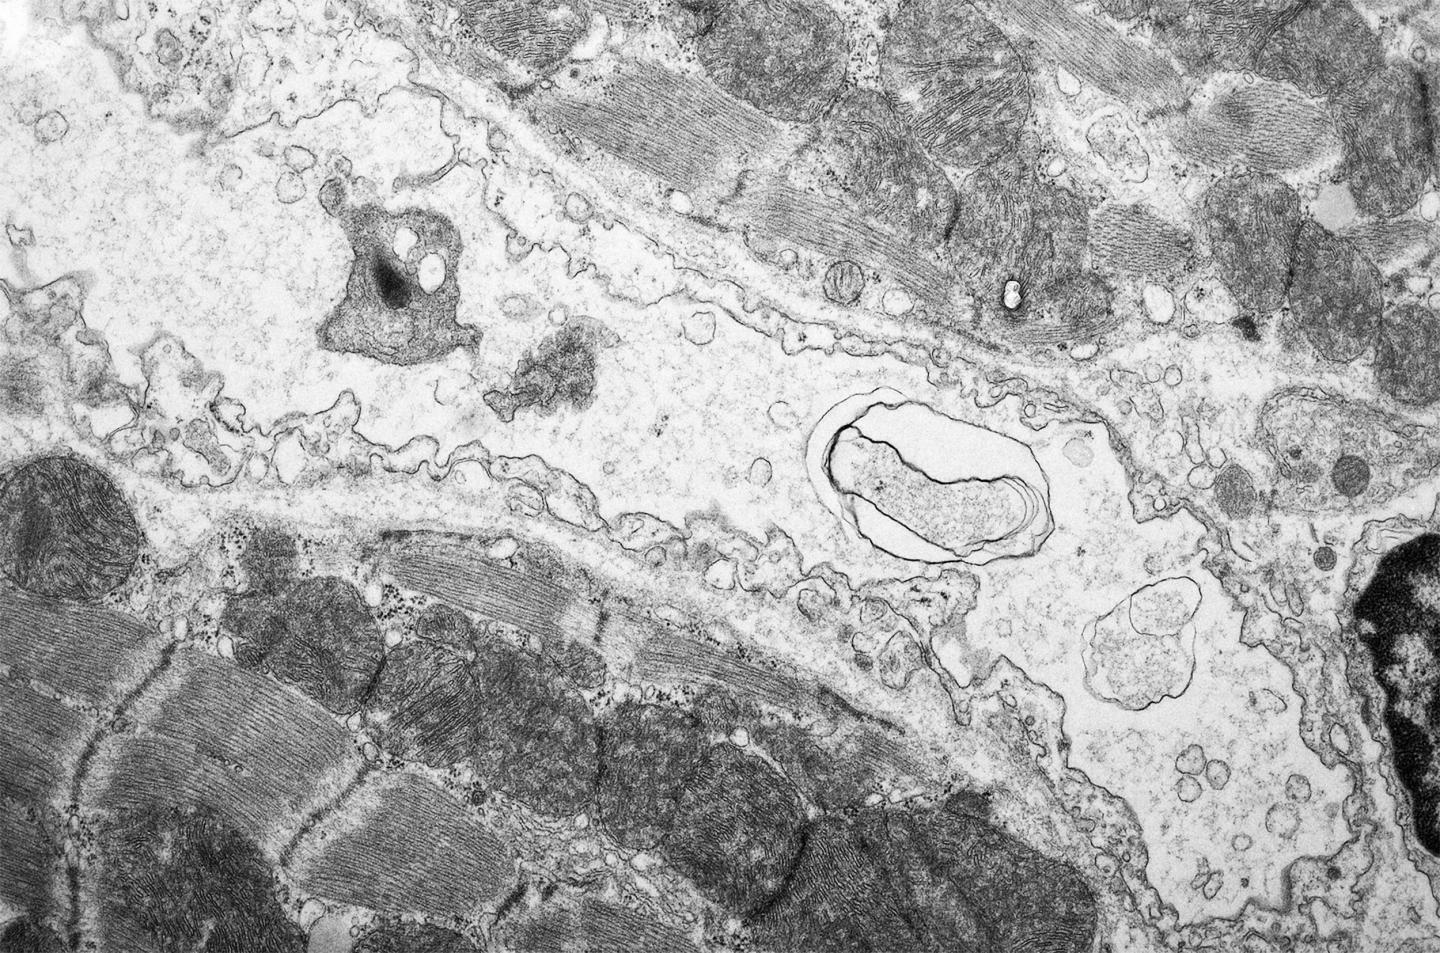

Doxorubicin treatment, which is commonly used in a variety of cancers, leads to cardiac atrophy and body wasting. The researchers found that in mouse heart, doxorubicin leads to blood vessel rarefaction, which was prevented by treatment with gene therapy using the VEGF-B growth factor.

"Our findings show, that especially the endothelial cells, which form the inner surface of the vessels in the heart, have an essential role in the protection against the cardiotoxicity. More preclinical studies are needed though for the development of VEGF-B gene therapy for cardiac protection in patients" elaborates Räsänen.